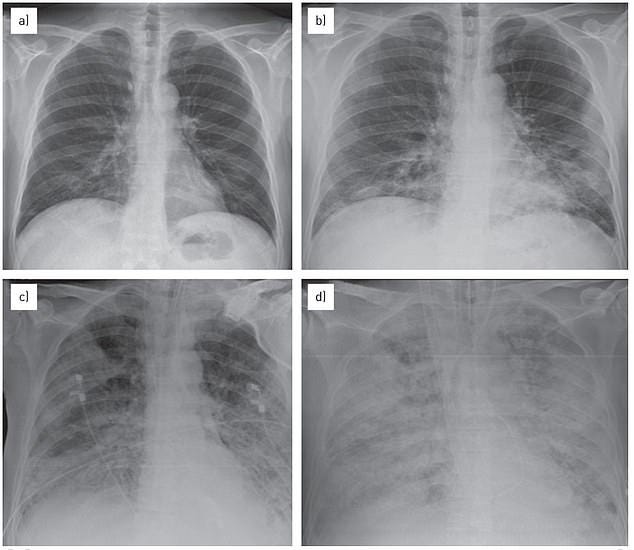

Doctors in parts of Massachusetts and Ohio are reporting a spike in child pneumonia cases similar to the outbreak spreading in China and parts of Europe.

In Warren County, just 30 miles outside Cincinnati, there have been 142 pediatric cases of the condition — dubbed 'white lung syndrome' — since August, a figure health officials there described as 'extremely high'.

Meanwhile, in western Massachusetts, physicians are seeing 'a whole lot' of walking pneumonia, a milder form of the lung condition, which is being caused by a mixture of bacterial and viral infections.

Neither outbreak is being caused by a novel pathogen and not all of the pneumonia cases are being caused by the same infection. Experts say a mixture of several seasonal bacterial and viral bugs are hitting at once, putting pressure on hospitals.

Patients in the county - which is home to around 200,000 people - have tested positive for mycoplasma pneumoniae, a bacterial lung infection for which some antibiotics are useless, adenovirus, a normally benign respiratory infections, and strep.